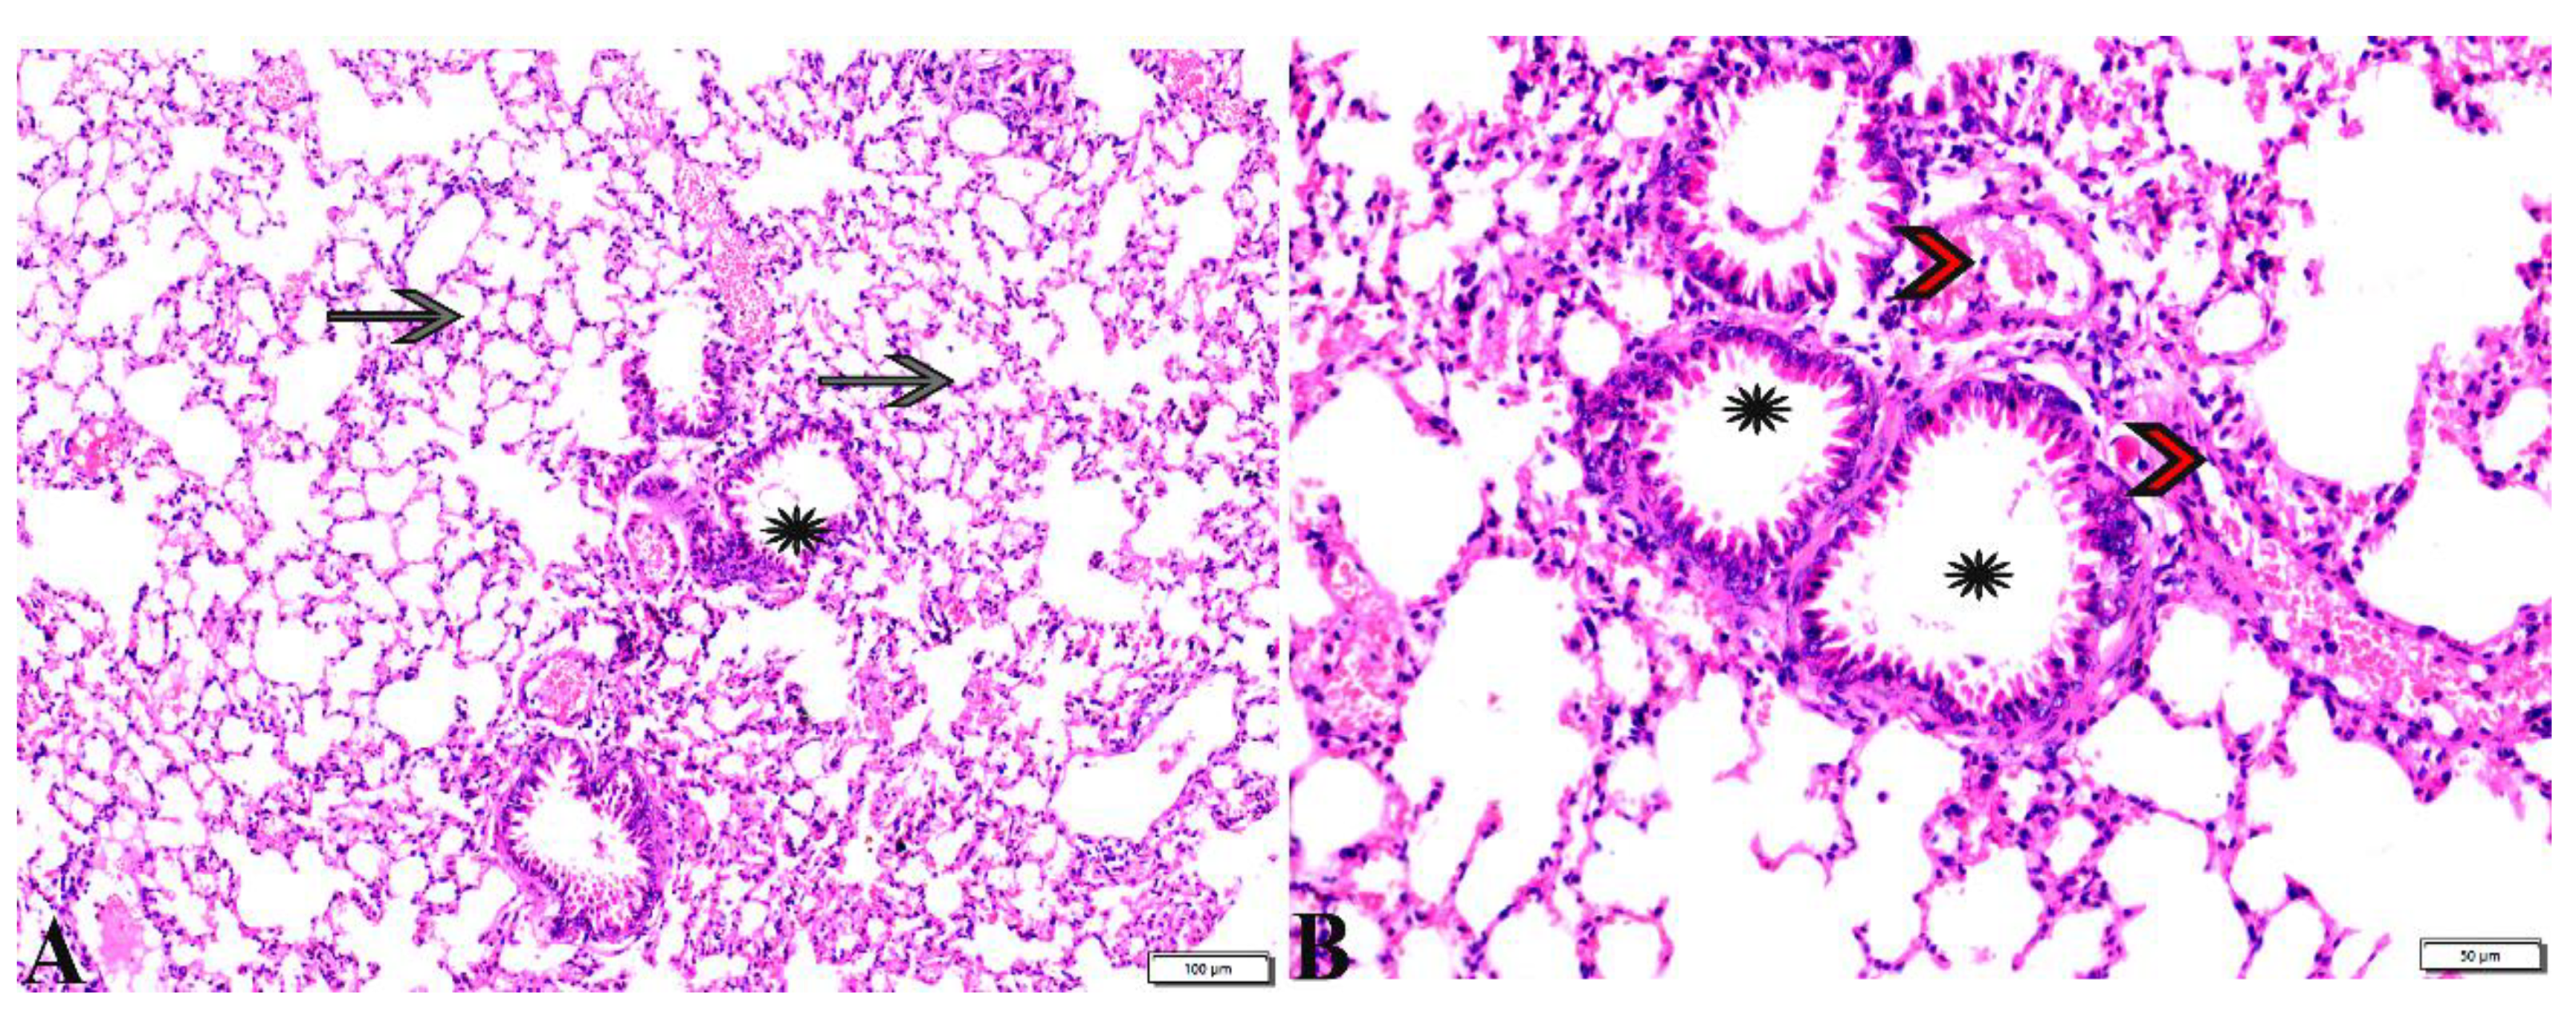

3.3. Histopathological Evaluation